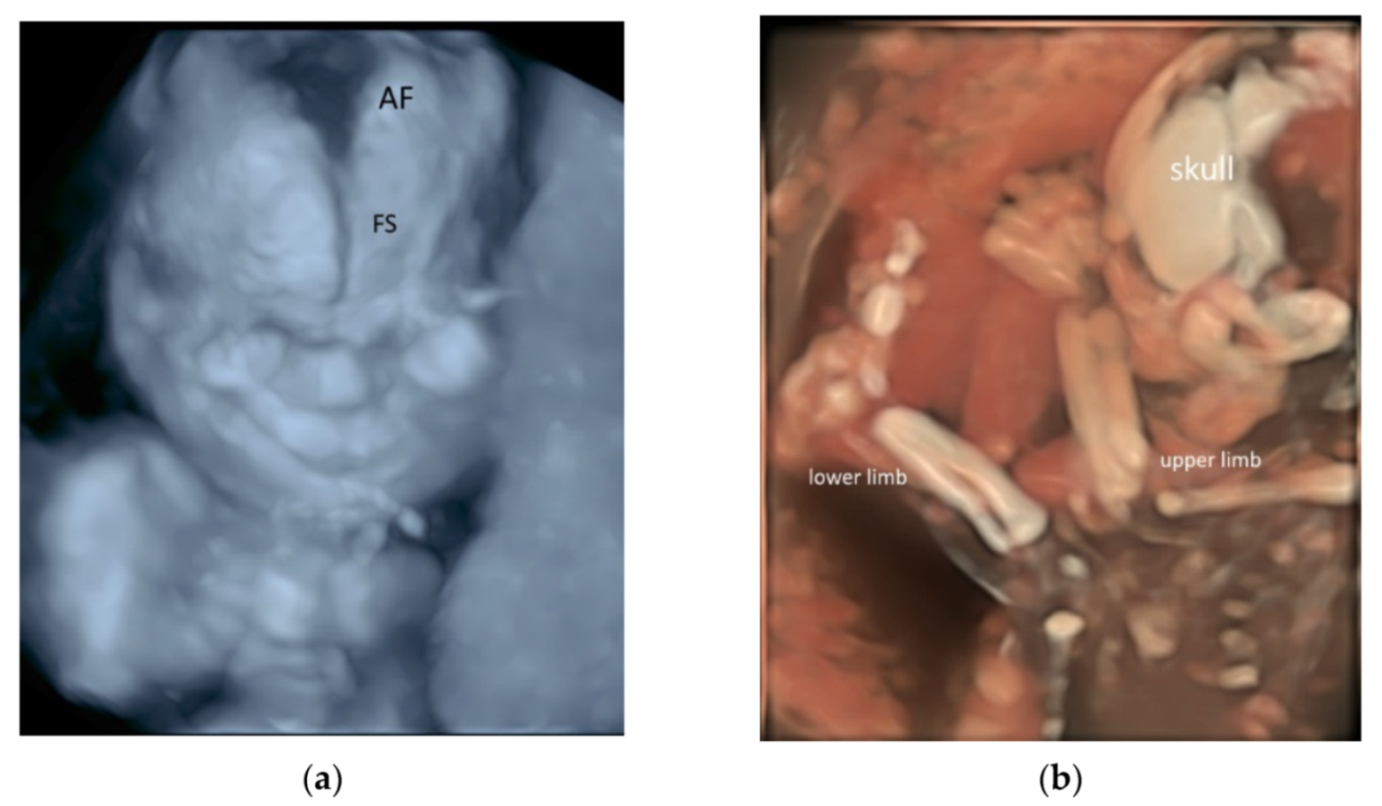

Three-dimensional (3D) rendering technology with skeletal mode can display skull, vertebrae, ribs, long bones and fingers [52] (Figure 11a,b and Video S10a,b). Prenatal assessment of the ribs and vertebral pattern can be performed by 3D ultrasound with skeletal mode (Figure 8a,b), albeit it is not a routine practice. A review of 39 studies including 75,018 healthy subjects and 6130 subjects with structural or chromosomal anomalies or adverse outcome showed an association between cervical ribs and other structural anomalies including esophageal atresia and anorectal malformation [53]. Abnormalities such as craniosynostosis [26,54], and extra ribs can be shown.

Figure 11.

Three-dimensional rendered images of the fetal skeleton at 20–22 weeks’ gestation showing: (a) X-ray mode of the skull bone with frontal suture (SS) and anterior fontanelle (AF), and (b) HD skeletal mode of the skull, bones of the upper and lower limbs.